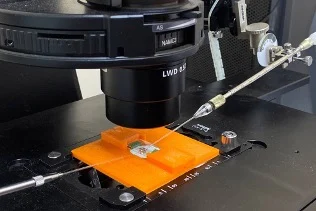

Офтальмоскопия и интегральная полуколичественная оценка состояния глазного дна

Электроретинография

Гистологические методы оценки изменений сетчатки и зрительного нерва